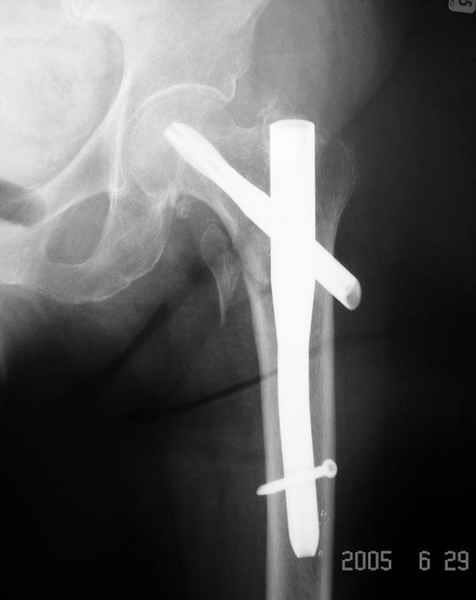

Второй случай тоже репозиция из малого доступа, больному 19 лет, множественные огнестрельные повреждениия конечностей, живота и черепа, правая конечность холодная, без пульсации. Ортопедический диагноз: огнестрельный перелом правого бедра. При срочной ангиографии повреждения сосудов не подтвердилось, конечность из-за ургентности состояния больного зафиксирована временным наружным фиксатором и больной оставлен на операционном столе для срочной лапаротомии хирургической службой.

Больной долго оставался нестабильным, только на 14 день удалось заменить на антеградный интромедуллярный штифт TFN (trochanteric femoral nail) SmithNephew. После неудачной попытки закрытой репозиции, несмотря на использование "joystick", проксимальный стержень от

наружного фиксатора, (перелом начал срастаться) репозицию провели из малого доступа, затем остальные этапы операции.

Случай был представлен из-за того, что больного оперировали после наружной фиксации и был риск инфекцирования через места проведения стержней (на снимках), прошло больше 3 месяцев, выписан из амбулаторной службы из-за отсутсвия надобности дальнейшего наблюдения.